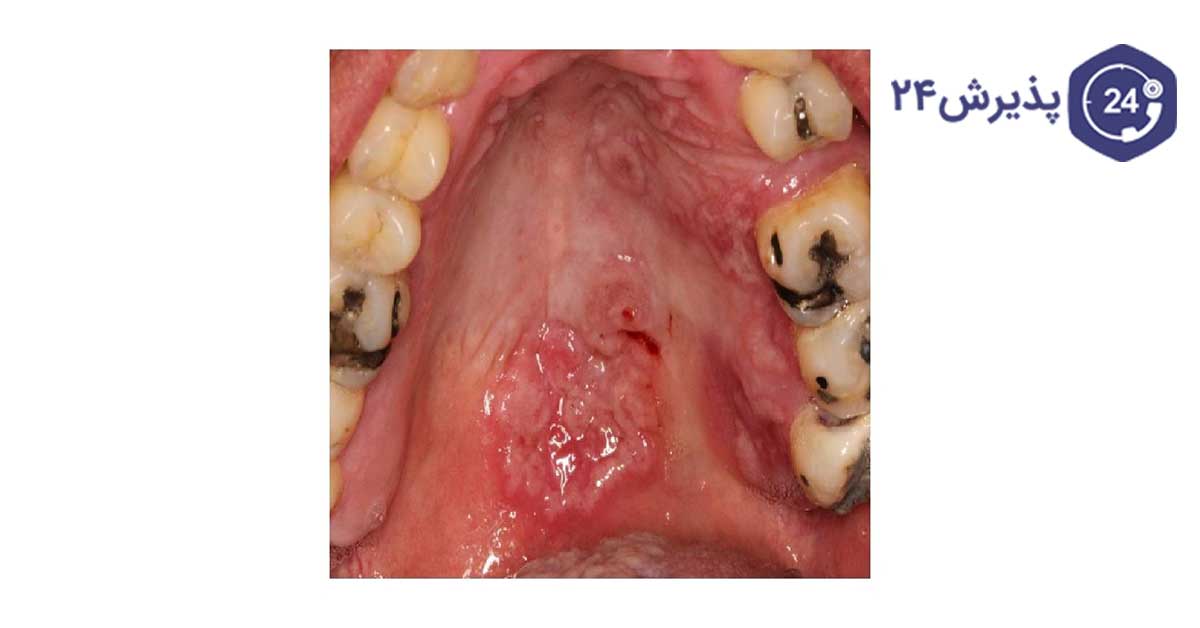

معمولترین و اولین علامت سیفلیس زخمهای کوچک است، به زخمهایی که در اثر سیفلیس ایجاد میشود شانکر گفته میشود. زخم سیفلیس ممکن است در نواحی تناسلی، روی آلت تناسلی یا در مقعد یا حتی در دهان ایجاد میشود. مهمترین ویژگی این زخمها این است که با درد همراه نیست و در برخی مواقع اصلاٌ فرد متوجه این زخمها نمیشود. زیرا در برخی موارد زخمها خود بهخود بهبود مییابند.

تصاویر بیماری سفلیس به شما نشان میدهد این بیماری چه عوارض و نشانههایی دارد.